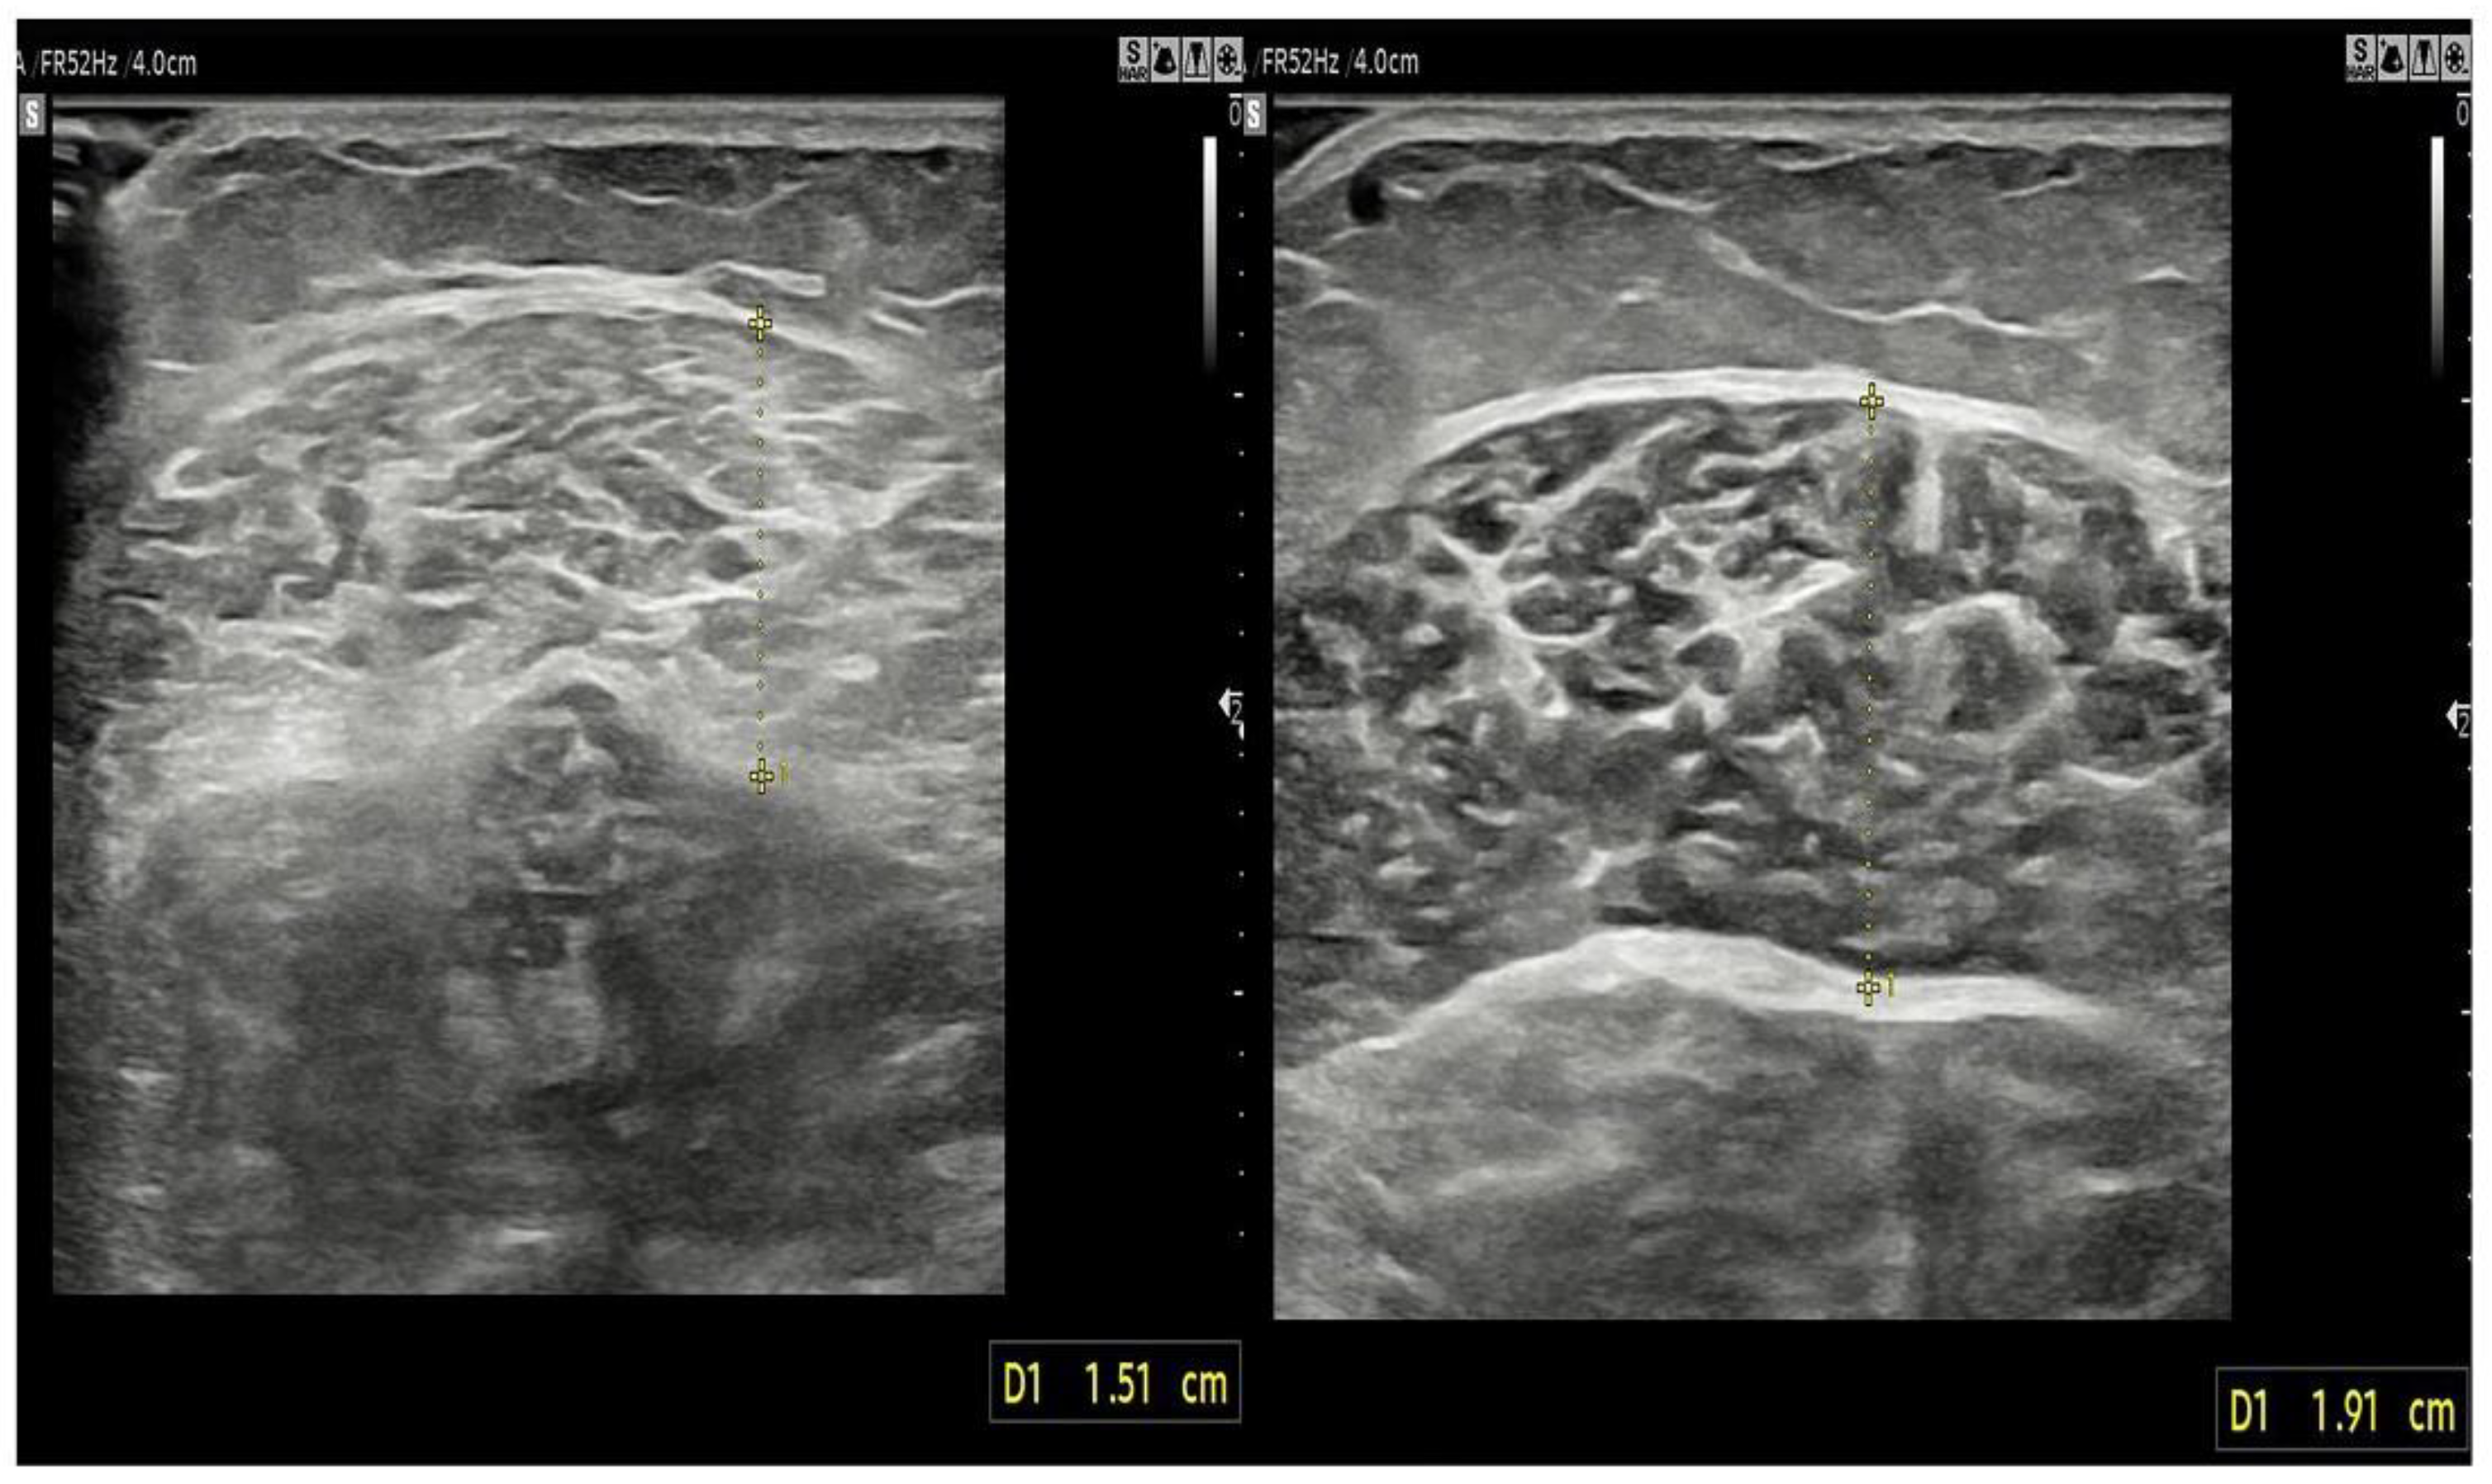

2.3.4. Stiffness and Thickness of the Muscle

| thickness (mm) | 17.65 ± 0.27 | 19.05 ± 0.28 | 0.008 | 0.145 (0.037~0.253) |